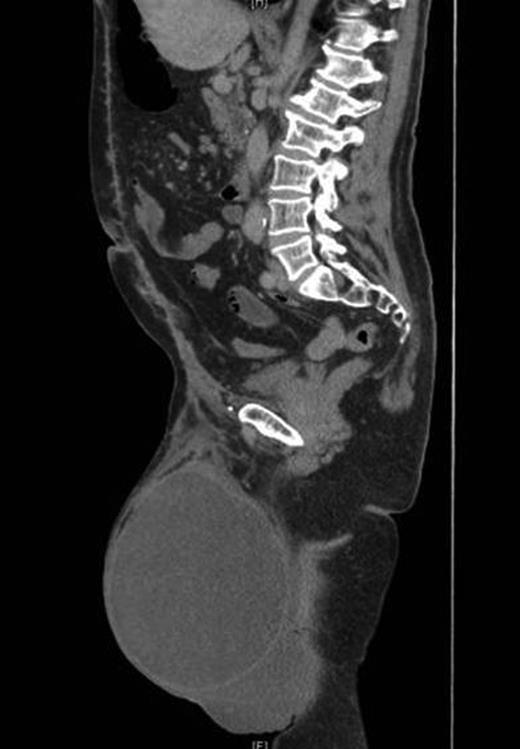

On follow-up after 8 weeks, the patient was in a very good general condition with intact hernia repair and laparotomy wound. He was found to have a moderate scrotal swelling (Fig. 3) which proved by CT scan to be a postoperative seroma (Fig. 4) which was managed conservatively.

Postoperative CT scan showing intact repair and clear fluid in the scrotum.